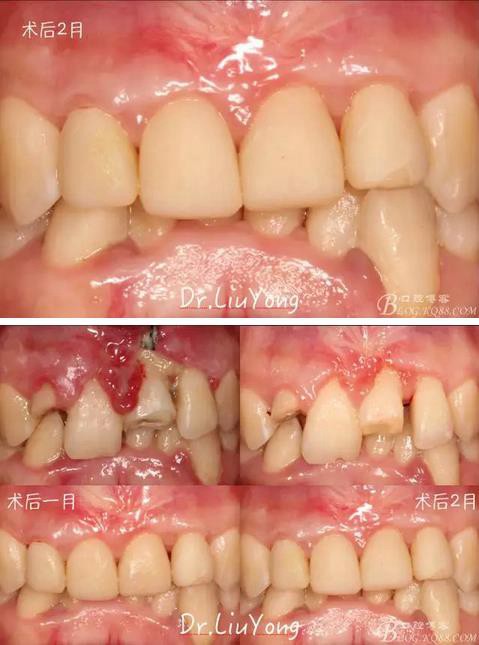

松動(dòng)牙固定一月后拆除,A1-B2無(wú)明顯動(dòng)度,但牙齦紅腫加重,給予全口齦上下潔治刮治術(shù),上藥,醫(yī)囑加強(qiáng)口腔衛(wèi)生,氯己定漱口液含漱。

術(shù)后兩周復(fù)查,牙齦紅腫明顯好轉(zhuǎn),探診不出血,但是此時(shí)A1唇側(cè)牙齦角形退縮1.5mm,B1唇側(cè)牙齦退縮3.5mm,B1遠(yuǎn)中牙齦乳頭萎縮明顯,B2近中牙齦萎縮約1mm,且A1B1B2牙齦退縮處角化牙齦幾乎缺失,同時(shí)上唇系帶直接牽拉于B1齦緣?;颊邽楦咝€女性,露齦笑,由于存在前牙區(qū)牙齦的高度嚴(yán)重不對(duì)稱及前牙牙冠過(guò)長(zhǎng)的問(wèn)題,因此嘗試通過(guò)膜齦手術(shù)改善患牙牙齦退縮。通過(guò)術(shù)前分析,A1唇側(cè)牙齦退縮屬于Miller分類第一類, B1唇側(cè)牙齦退縮屬于Miller分類第3類(B1遠(yuǎn)中牙齦乳頭為2類,Nordland and Tarnow分類法),B2唇側(cè)牙齦退縮屬于Miller分類第3類,由于擬采用冠向復(fù)位瓣的方式治療牙齦退縮,因此需要先行上唇系帶修整術(shù),解除上唇系帶帶來(lái)的過(guò)大牽引力。

術(shù)后兩周,復(fù)查,A1達(dá)到了完全的根面覆蓋,B1牙齦退縮由原來(lái)的3.5mm減少到1mm,B2近中牙齦也得到部分的恢復(fù),同時(shí)所有牙齦邊緣都通過(guò)手術(shù)增厚。如上圖

臨時(shí)修復(fù)體戴入后1月,復(fù)查,唇側(cè)觀如上圖

膜齦手術(shù)后2月復(fù)查,可以明顯觀察到,B12之間的牙齦乳頭明顯高度增加,黑三角得到很大改善,如下圖: